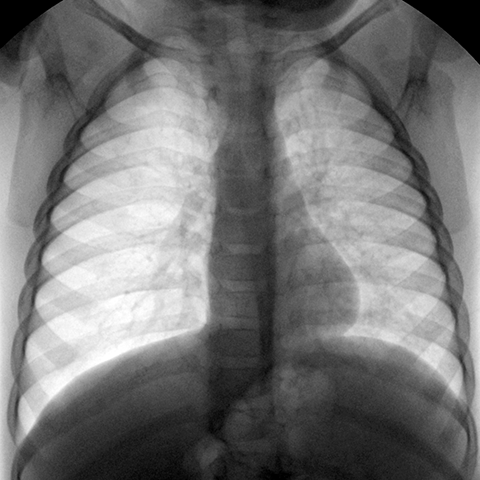

支气管异物Foreign body in Bronchus [2 of 3]